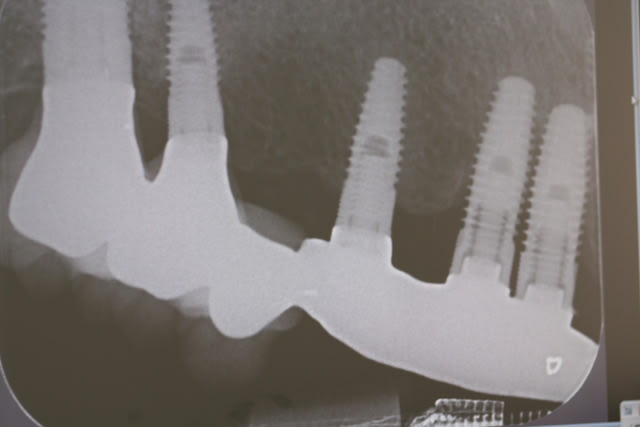

Exemple d'un bridge que j'ai repris il y a quelques mois, posé il y a 5 ans par un gars très renommé de ma région, le dentiste des stars .

Ne pas oublié qu'on apprend de ses erreurs, mais aussi de celles des autres, et que donc d'autres aprennent aussi de nos erreurs ...